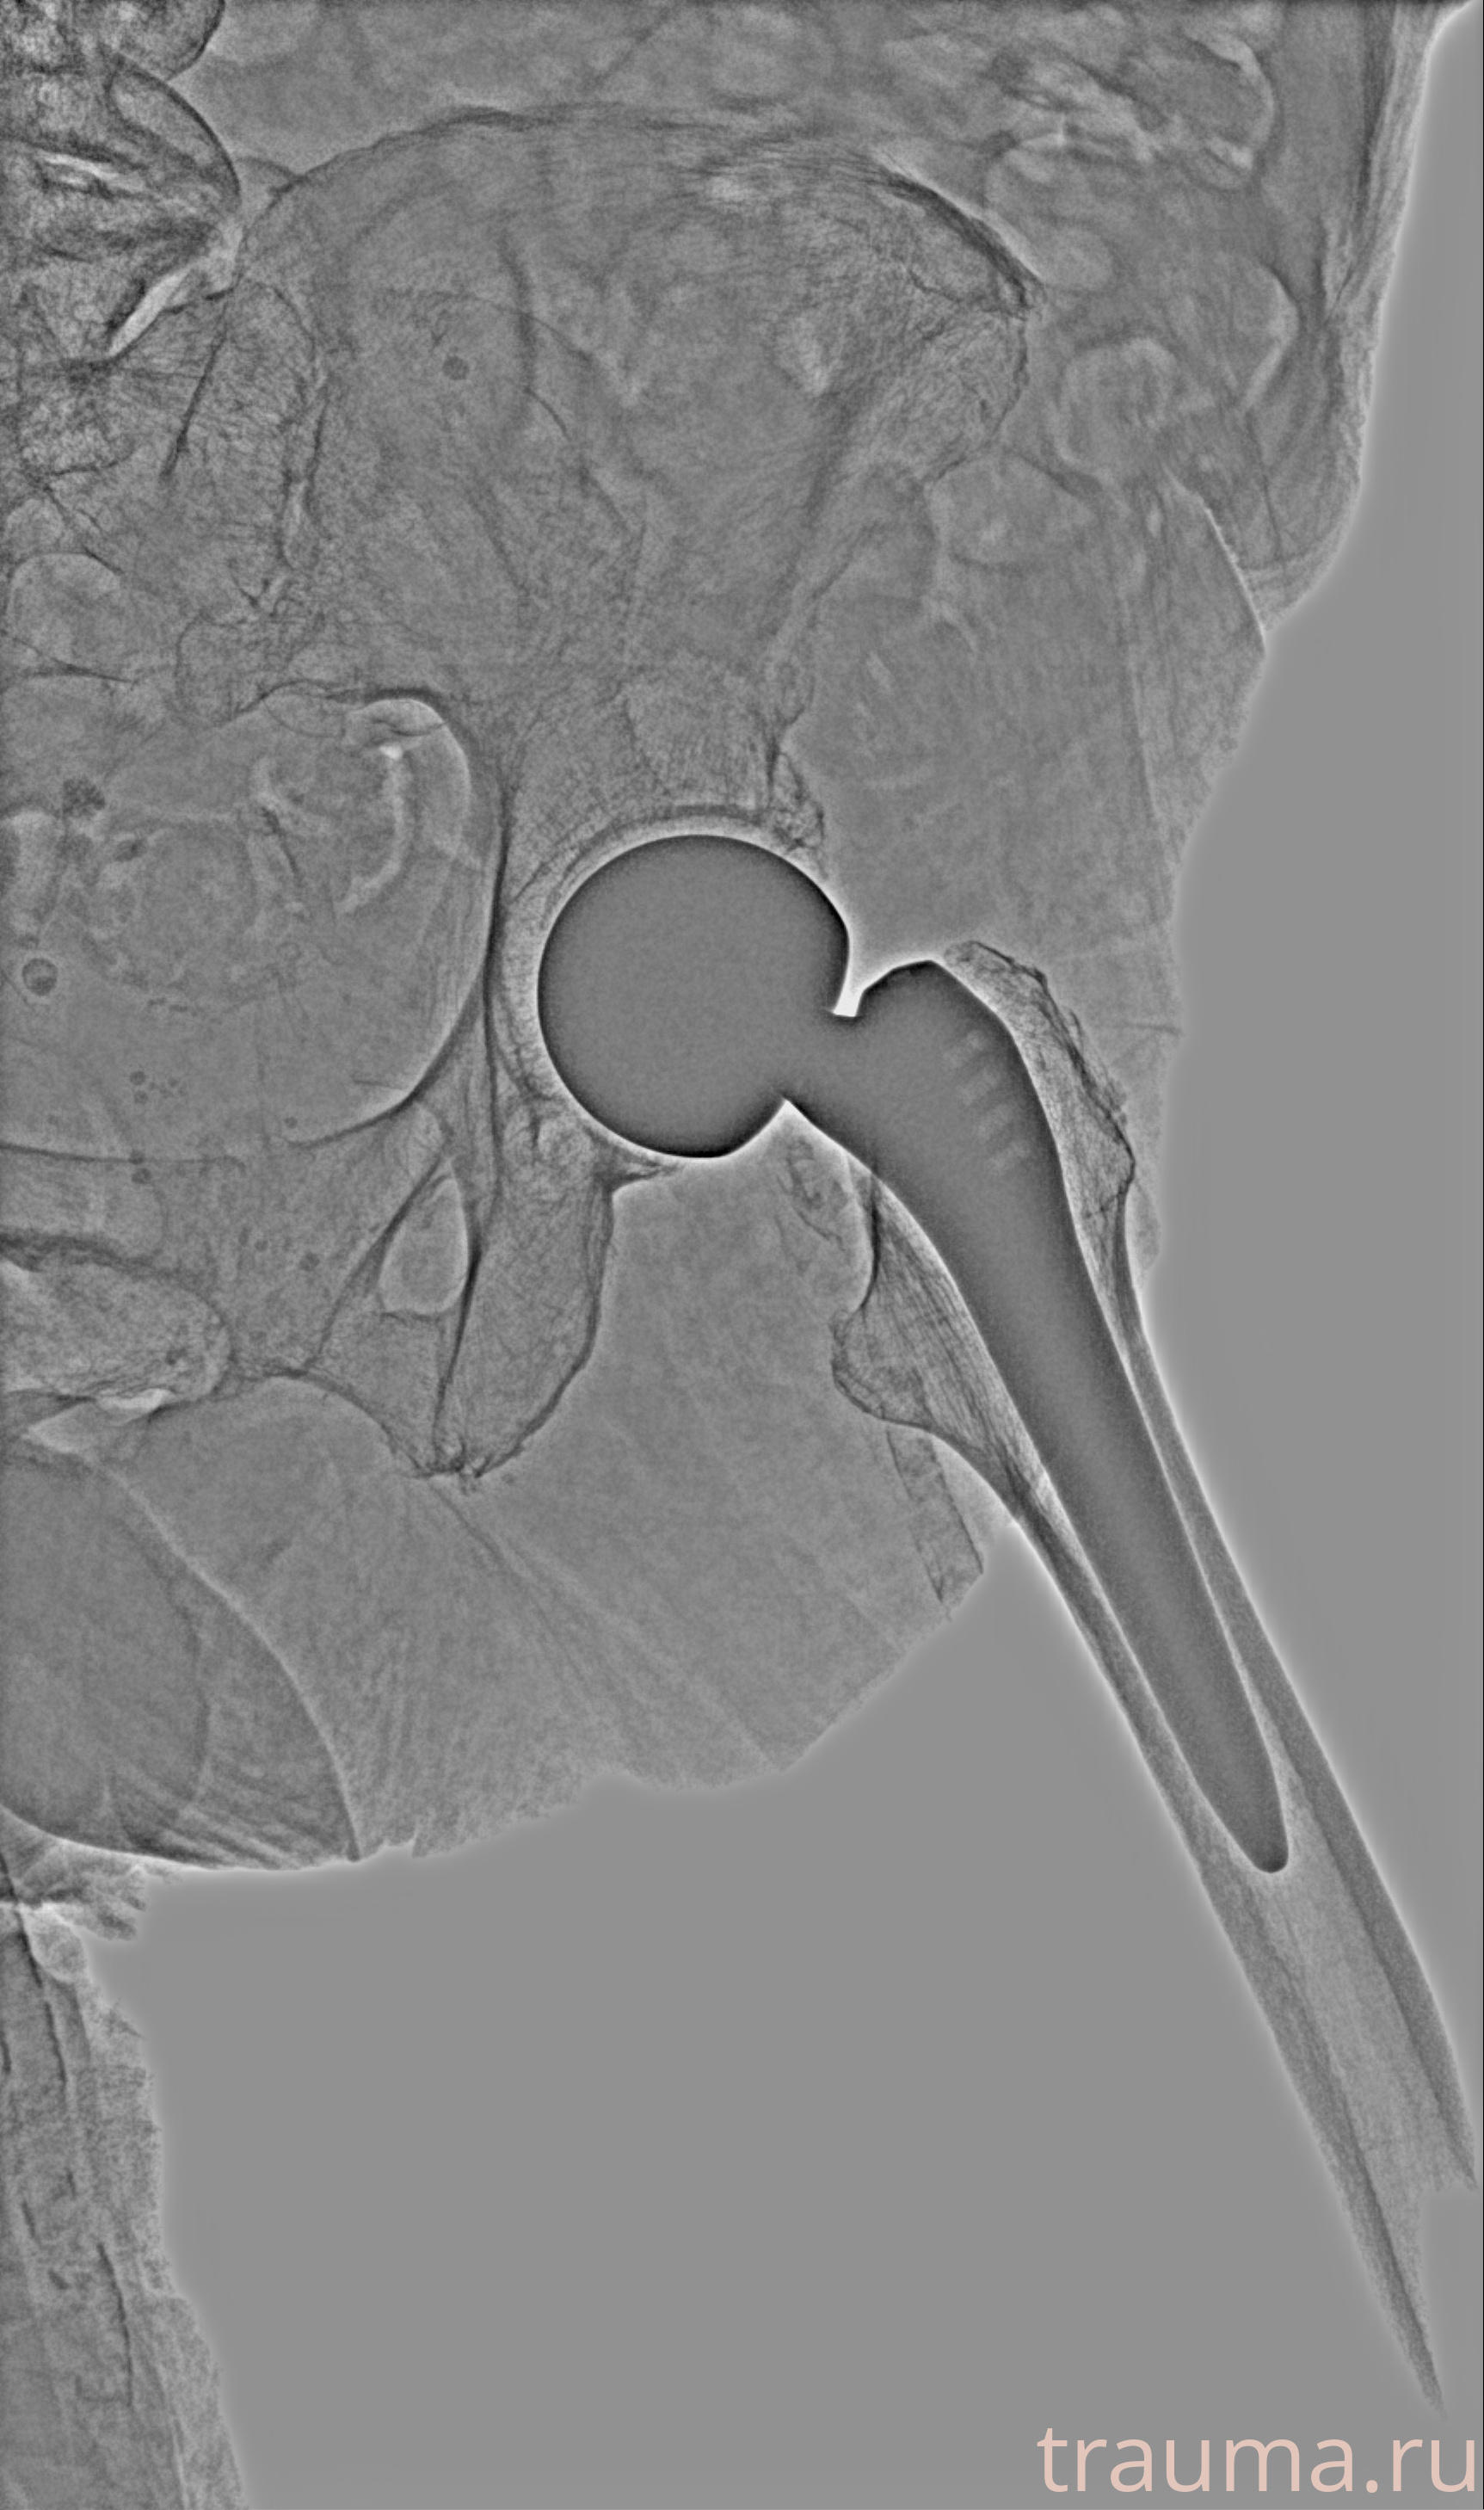

Рентгенограммы

Рентген на дому: по вашему адресу приезжает врач-рентгенолог, травматолог-ортопед с мобильным рентгеновским аппаратом, проводит диагностику травмы или заболевания, делает необходимые рентгенограммы, дает рекомендации по дальнейшему лечению. Получить качественные снимки в домашних условиях возможно благодаря уникальной методике, разработанной МосРентген Центром для института  Склифосовского